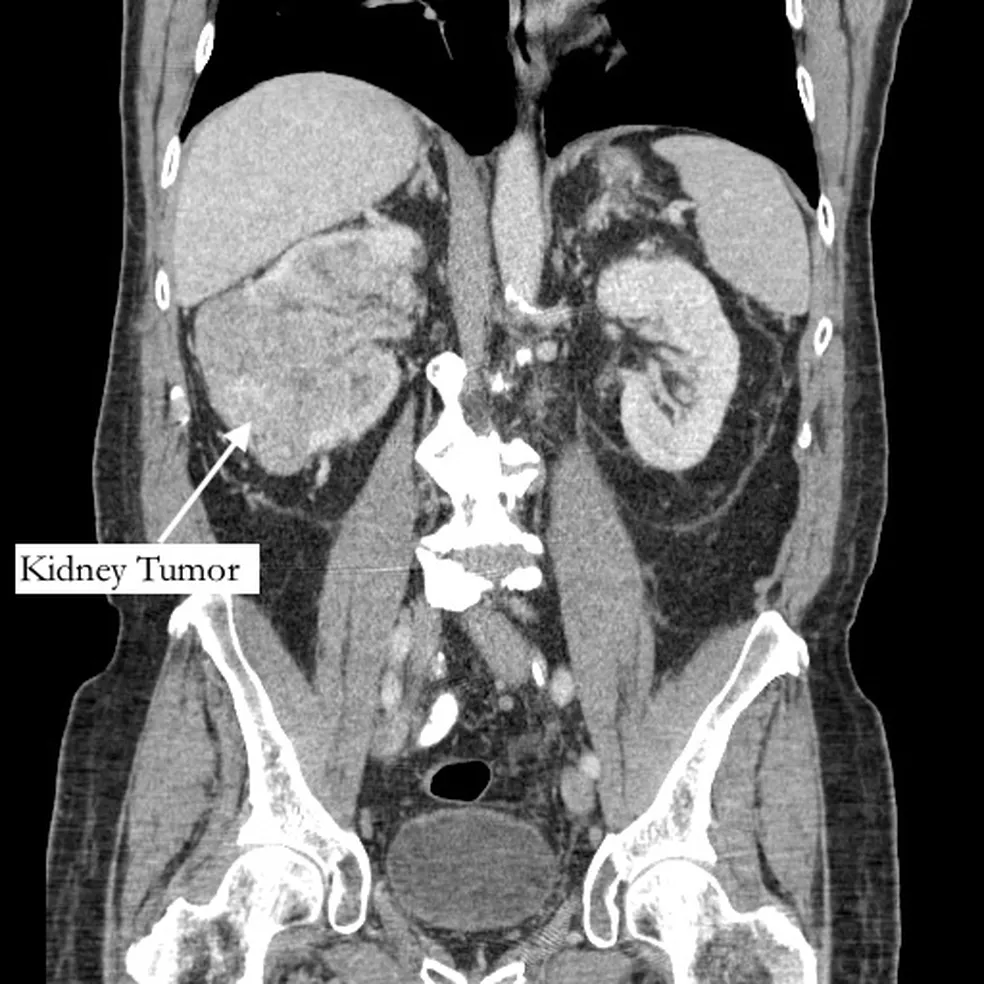

Tomografia de Bernstein mostrando seu tumor no rim. — Foto: Northwell Health/Divulgação

Segundo o jornal “New York Post”, Richard Bernstein, 42, sentia a dor havia cinco anos, e pensava que se tratava de uma fratura, mas recebeu o diagnóstico de grande tumor no rim e de um trombo tumoral, um tumor que se estende até um vaso sanguíneo.

O exame, encaminhado a um urologista, identificou ainda um trombo (coágulo no sangue) que cresceu através da veia renal e preenchia a veia cava, que drena sangue para o coração, e tinha 99% das artérias da coronária bloqueadas, além do fígado quase entrando em falência.